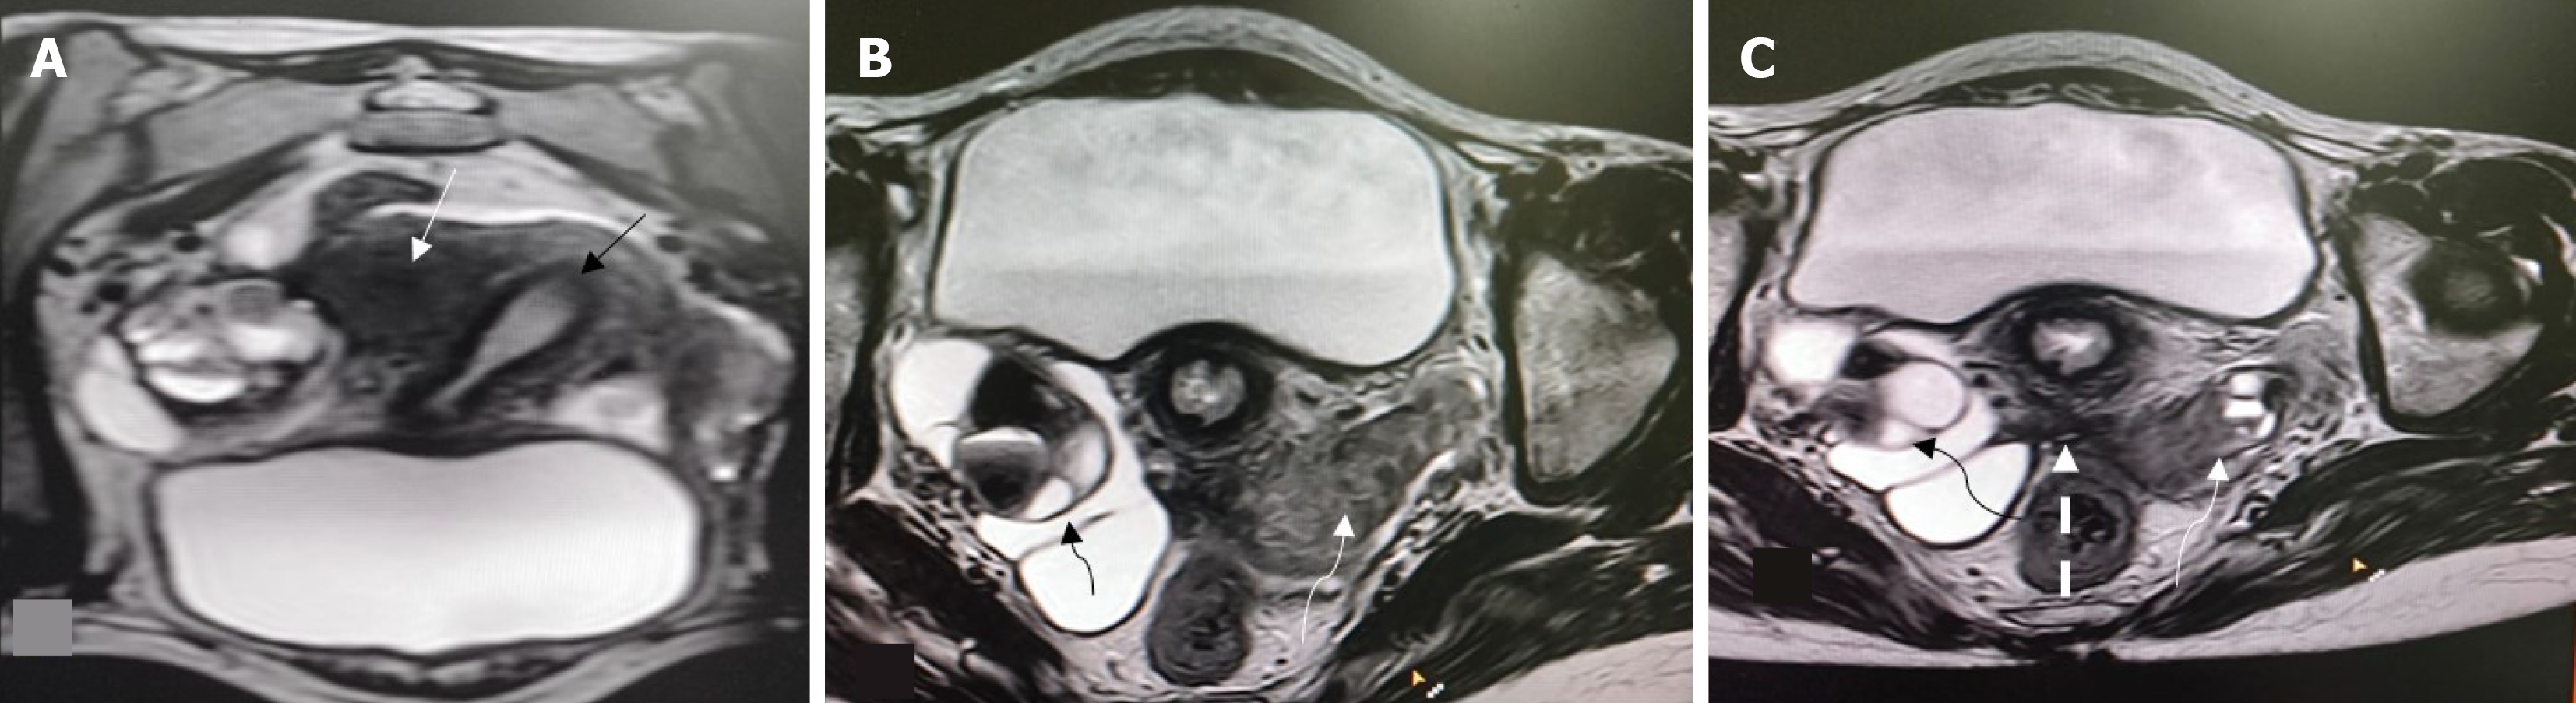

Overall, 22 patients had MRI findings consistent with endometriosis. Peritoneal disease (P1-P3) was not identified in this series. Ovarian endometriomas were present in 16 patients (21.3%), most commonly in the 3-7 cm range (O2, 12 patients; 16.0%). Tubo-ovarian adhesions or involvement (T2-T3) occurred in 11 patients (14.7%) (Figures 1, 2 and 3). Deep endometriosis nodules were observed primarily in the parametrial/uterosacral compartment (B) in 6 patients (8.0%). No rectosigmoid (C) or anterior compartment (A) endometriosis lesions were seen. Adenomyosis was identified in 4 patients (5.3%; diffuse in 2, focal in 2). A summary is presented in Table 2.

Table 3 highlights the association between uterine anomaly type, outflow obstruction, and the presence of endometriosis. Endometriosis was more frequently observed in patients with complex uterine anomalies, particularly U3c (bicorporeal septate uterus), U5a (aplastic uterus with a functional rudimentary cavity), and U0 (arcuate uterus), whereas a markedly low prevalence was noted in U5b (aplastic uterus without a functional cavity). A statistically significant association was seen between uterine category and endometriosis (P = 0.006).

With respect to associated anomalies, vaginal aplasia (V4) showed a significantly lower prevalence of endometriosis compared to patients with a normal vagina (P = 0.019), while cervical anomaly subtype did not demonstrate a statistically significant association. Overall, these findings suggest that functional endometrial tissue combined with altered outflow or complex uterine morphology plays a key role in determining the distribution of endometriosis in patients with Mullerian anomalies. Patients with a rudimentary horn containing a functional cavity had a significantly higher prevalence of endometriosis compared to those without a rudimentary horn (66.7% vs 26.1%, P = 0.036).

Among the 75 patients evaluated, obstruction was identified in 13 patients (17.3%). Within uterine anomaly groups (U), obstruction was most frequent in U3c anomalies, where 6 of 13 patients (46%) demonstrated obstruction. The presence of genital tract obstruction showed a strong correlation with endometriosis, with affected patients demonstrating nearly threefold higher prevalence compared to those without obstruction (61.5% vs 22.6%, P = 0.005). In this subgroup, obstruction affected both endometriosis (3/7; 43%) and non-endometriosis (3/6; 50%) patients. In U0 uteri (arcuate), 2 of 4 patients affected (50%), split equally between endometriosis (1/3) and non-endometriosis (1/1). U4a had obstruction in 1 of 2 patients (50%), single patients showed signs of obstruction in each group of U4b, U5a, U6. It was rare in U2a (1/14; 7%) and U5b (1/25; 4%). Across cervical categories (C), obstruction occurred predominantly in patients with normal morphology (C0), where 10 of 29 patients (34.5%) had endometriosis. In C2, 7 of 14 patients had endometriosis, whereas severe anomalies (C4) were associated with endometriosis in 4 of 29 patients (13.8%). Despite these endometriosis distributions, obstruction overall remained infrequent and did not cluster within any specific cervical subtype. Vaginal morphology similarly showed limited correlation with obstruction. Most patients with normal vaginal anatomy (V0) did not exhibit obstruction, despite 18 of 46 having endometriosis (39.1%). Among those with V4 anomalies, endometriosis was identified in 4 of 29 patients (13.8%). Overall, obstruction occurred sporadically across uterine, cervical, and vaginal classifications. Obstruction was most frequent in U3c (46% of that subgroup) but was distributed among both endometriosis and nonendometriosis patients.

Previous works have also showed that specific morphologies (unicornuate uteri) may have higher endometriosis prevalence even among nonobstructive anomalies, suggesting morphologyspecific risks[19]. Our findings reiterate that uterine morphology and the presence of functional endometrium influence the likelihood of endometriosis. The distribution of endometriosis varied across uterine anomaly types, with higher prevalence noted in complex configurations such as bicorporeal septate uterus and aplastic uterus with a functional rudimentary cavity. Vaginal aplasia (V4) was associated with a significantly lower prevalence of endometriosis compared with normal vaginal anatomy (P = 0.019). By integrating the ESHRE/ESGE classification of Mullerian anomalies with Enzian-based mapping of endometriosis, this study demonstrates how specific uterine anatomy and functional outflow characteristics influence both the likelihood and distribution of endometriotic disease.